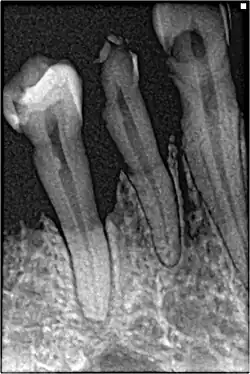

In periodontal health, the alveolar bone surrounds the teeth and forms the bony socket that supports each tooth. The buccal and lingual plates and lining of the sockets are composed of thin, yet dense compact or cortical bone.[3] Within the cortical plates and dental sockets lies cancellous bone, a spongy or trabecular-type bone which is less dense than compact bone.[6] The anatomic landmarks of the alveolar process includes the lamina dura, the alveolar crest, and the periodontal ligament space.[9]

If disease is identified through this process, then a full periodontal analysis is performed, often by dental hygienists, oral health therapists, or specialist periodontists. This involves full mouth periodontal probing and taking measurements of pocket depths, clinical attachment loss and recession. Along with this other relevant parameters such as plaque, bleeding, furcation involvement and mobility are measured to gain an overall understanding of the level of disease. Radiographs may also be performed to assess alveolar bone levels and levels of destruction.[40]